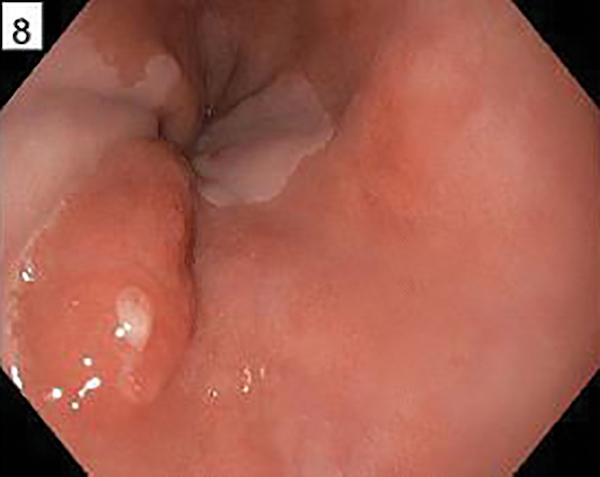

A 65-year-old man presents for evaluation of long-standing GERD. A hiatal hernia and lower esophageal mucosal changes are found on his EGD [FIGURE]. Biopsies at the top of the mucosal changes showed specialized Barrett’s mucosa with focal changes indefinite for dysplasia. Which of the following is the best next step in management?

This patient presents with long-segment Barrett’s esophagus with indefinite dysplasia. Reactive changes due to acid reflux can mimic dysplasia. Therefore, optimizing reflux therapy and ensuring compliance can minimize the reactive changes that may be mistaken for dysplasia. However, repeat endoscopy should not be delayed beyond 6 months, as dysplasia and intramucosal tumor can be missed on initial biopsy due to sampling error in the setting of indefinite dysplasia. Radiofrequency ablation can be done in the future if dysplasia, confirmed by 2 specialized pathologists persists after an adequate trial of PPI, but not on initial diagnosis of indefinite dysplasia. As many as 80% of patients with indefinite dysplasia will show regression to nondysplastic Barrett’s esophagus on subsequent endoscopies. However, endoscopic surveillance is warranted even if this regression occurs.